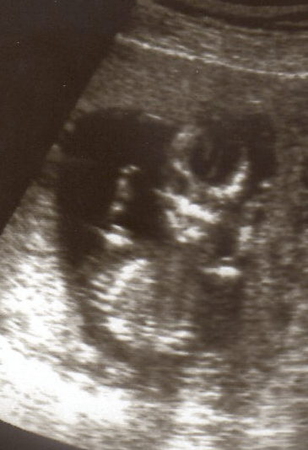

первая встреча!

Мало весит малыш...(( "водянка яичка"